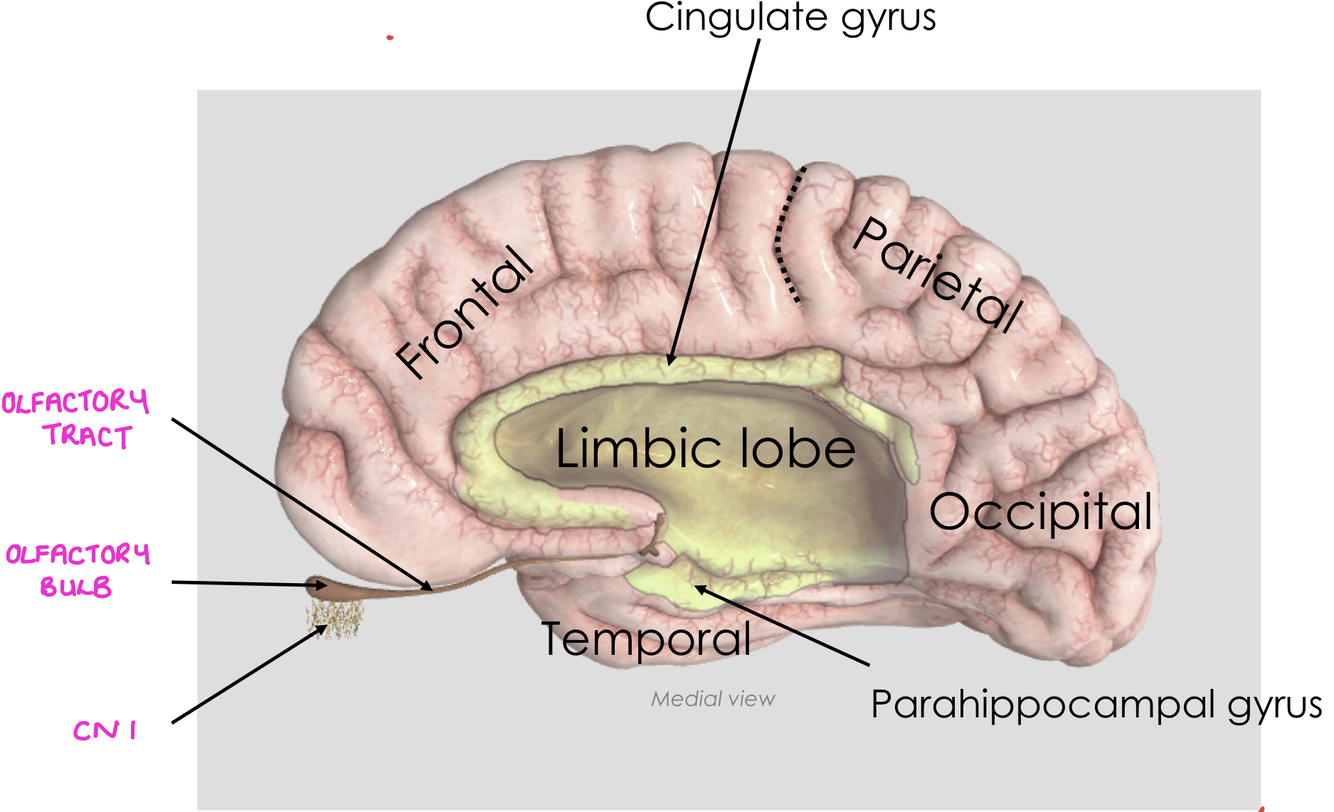

What are the following structures?

What is significant about their relationship with the limbic system?

The olfactory tract is involved with the limbic system

smell can trigger emotions, memories and autonomic nervous system responses

the olfactory bulb and olfactory tract are outgrowths of the telencephalon - olfaction is the only sensory system to bypass the thalamus on the way to the cerebral cortex